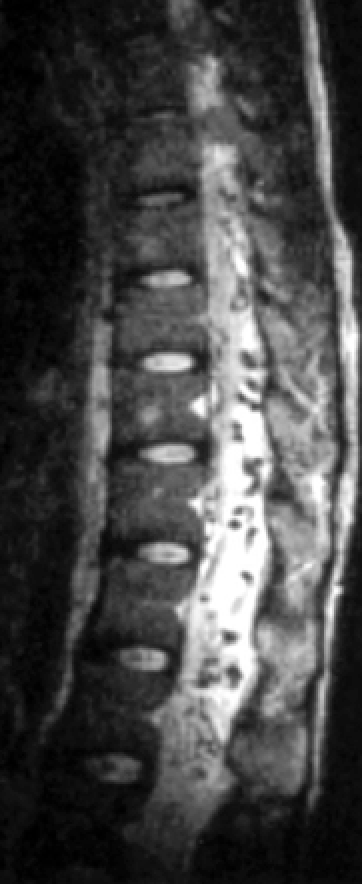

8yo with first time seizure

Diagnosis?

Other associated findings?

Sturge-Weber Syndrome

Congenital phakomatosis with hemangiomatosis of face (CN V distribution), choroid of the eye, and leptomeninges

“Tram-track” Cortical calficifications, often with parenchymal volume loss due to vascular steal